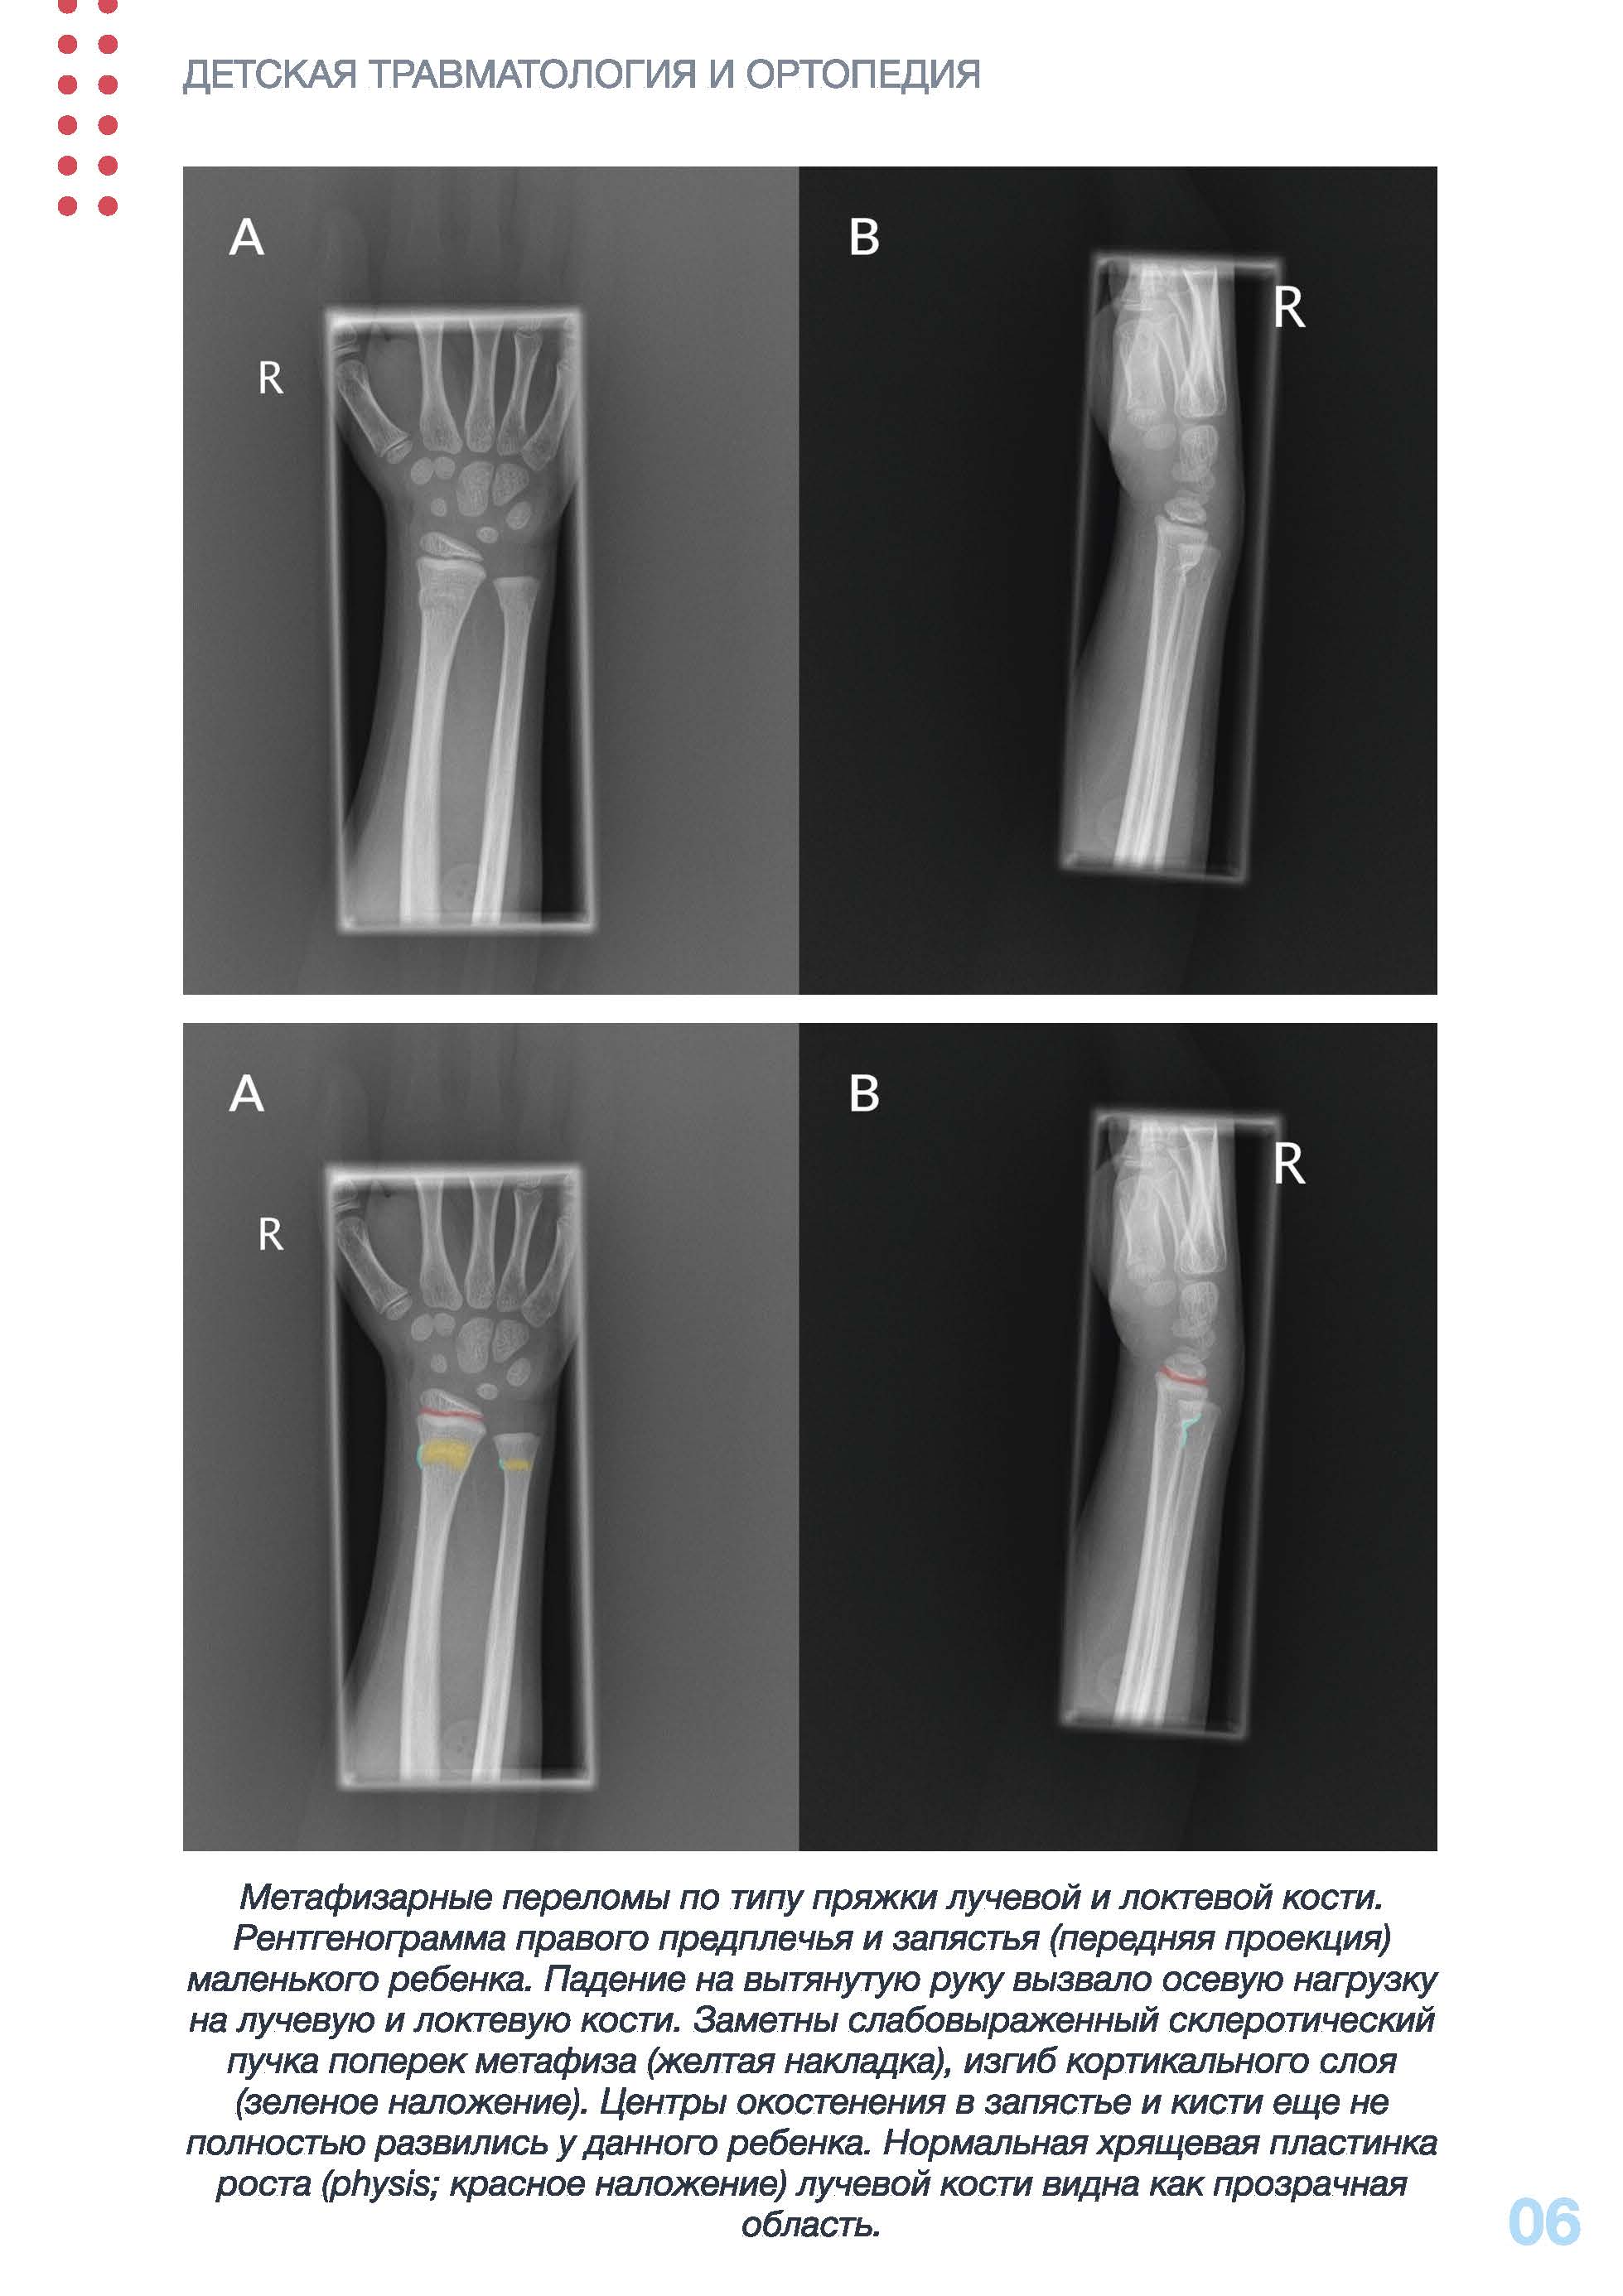

Переломы у детей часто имеют отличительные особенности из-за

уникальных свойств растущих костей. Поскольку надкостница в растущих

костях толще и прочнее, чем у взрослых, дети более склонны к неполным

переломам, таким как переломы по типу зеленой ветки (Сгееп stick fracture), переломы по типу пряжки (Buckle fracture/torus fracture) или

переломы по типу изгиба (bowing fracture). Кроме того, переломы у детей

заживают быстрее, чем у взрослых, поскольку надкостница у детей

метаболически активна. Переломы Солтера-Харриса затрагивают

эпифизарную пластинку, также известную как пластинка роста или физис

длинных костей, и случаются только у детей и подростков, чей рост

скелета еще не завершен. Данные переломы классифицируются в

зависимости от степени повреждения пластинки роста и вовлечения

суставов.